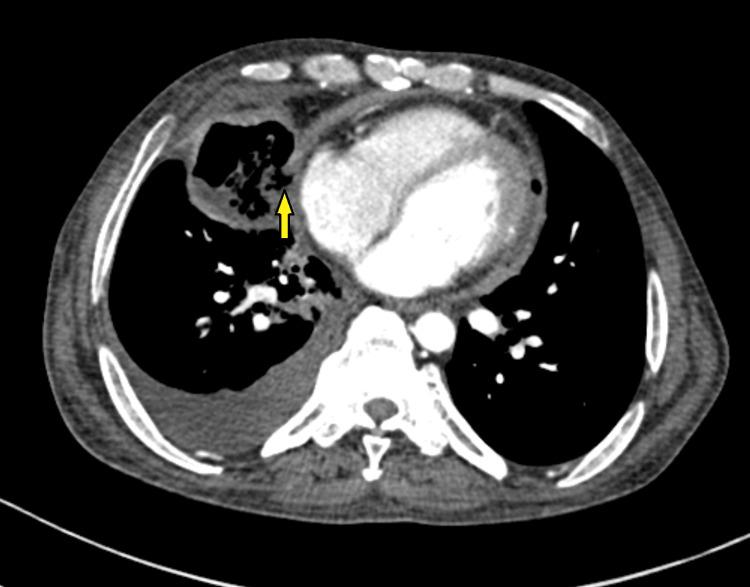

Pneumopericardium due to bronchopericardial fistula formation is a rare complication secondary to necrotizing pneumonia. Several such cases are reported due to different suppurative bacterial infections. Persistent fistulous communication has been reported to lead to tension pneumopericardium and hemodynamic instability, requiring urgent intervention such as pericardial drainage. A 41-year-old male patient, known to have chronic kidney disease and diabetes mellitus, presented with acute respiratory symptoms. Upon admission, the patient was febrile and required oxygen support via nasal prongs. A chest X-ray showed fibrocavitatory changes on the right side, with patchy air shadowing around the cardiac silhouette and a continuous diaphragm sign. A contrast-enhanced computed tomography (CECT) thorax revealed extensive areas of consolidation with necrotic areas within, forming a thin-walled cavity involving the right middle lobe. Also, suspicious communication of this cavity with the pericardial cavity along the right atrium was seen, with minimal pericardial collection and air foci within. The pleural fluid culture showed growth of . According to the antibiotic sensitivity report, the patient was started on IV meropenem and gentamicin for 21 days while monitoring kidney functions. The patient clinically improved on antibiotics, and follow-up radiological investigations showed resolution of pneumopericardium. In this patient, pneumopericardium was mild, and there was no evidence of tension pneumopericardium. Thus, conservative management with antibiotics was provided, with successful resolution. Unlike this case, if evidence of tension pneumopericardium had been present, emergency interventions for decompression would have been required, and these cases would have had a poor prognosis. This case demonstrates the importance of high suspicion and early diagnosis of pneumopericardium in patients with necrotizing pneumonia. Prompt treatment in these patients can prevent further life-threatening sequelae.

支气管心包瘘形成导致的气胸是坏死性肺炎继发的罕见并发症。已有数例因不同化脓性细菌感染导致的此类病例报道。据报道,持续性瘘管相通会导致张力性气胸和血流动力学不稳定,需要紧急干预,如心包引流。一名41岁男性患者,已知患有慢性肾病和糖尿病,出现急性呼吸道症状。入院时,患者发热,需要经鼻吸氧支持。胸部X线显示右侧有纤维空洞性改变,心脏轮廓周围有斑片状气影及连续膈征。胸部增强计算机断层扫描(CECT)显示广泛实变区域,内有坏死区域,形成一个累及右中叶的薄壁空洞。此外,可见该空洞沿右心房与心包腔可疑相通,心包内有少量积液和气灶。胸水培养显示……生长。根据抗生素敏感性报告,患者开始静脉输注美罗培南和庆大霉素21天,同时监测肾功能。患者使用抗生素后临床症状改善,后续影像学检查显示气胸已消退。在该患者中,气胸较轻,无张力性气胸证据。因此,给予抗生素保守治疗,获得成功治愈。与该病例不同的是,如果存在张力性气胸证据,则需要进行紧急减压干预,而这些病例预后较差。该病例证明了对坏死性肺炎患者高度怀疑和气胸早期诊断的重要性。对这些患者进行及时治疗可预防进一步危及生命的后遗症。